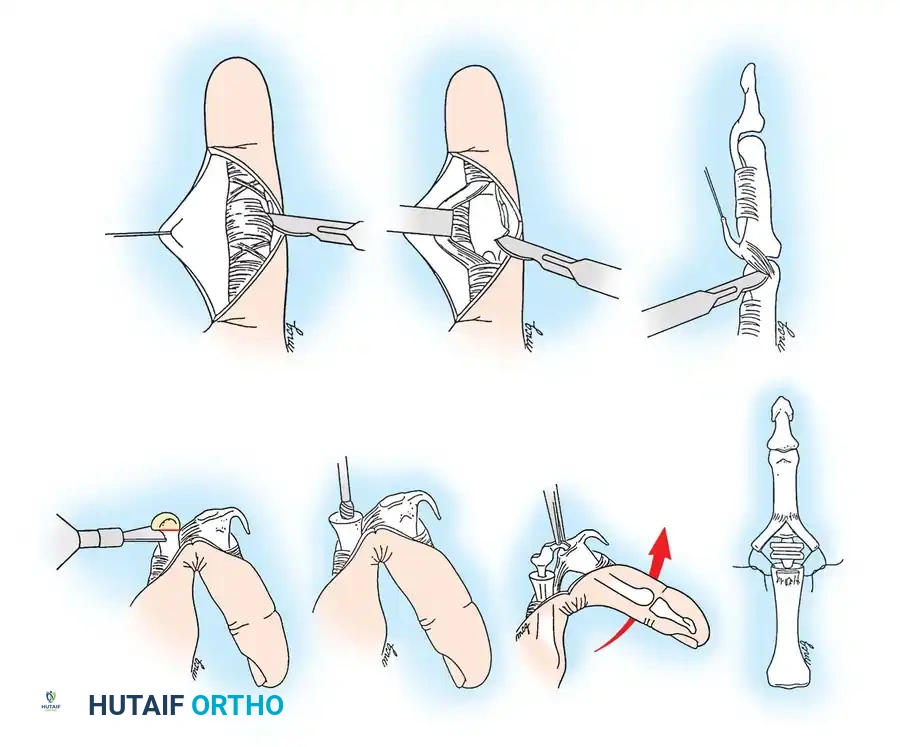

Correction of PIP Hyperextension Deformity (Beckenbaugh FDS Tenodesis)

This technique utilizes a slip of the FDS to create a volar tether, preventing PIP hyperextension while allowing active flexion.

TECHNIQUE 70-1: Beckenbaugh

Incision and Exposure: Make a volar zigzag (Bruner) incision over the middle and proximal phalanges. Meticulously avoid damaging the digital neurovascular bundles, which may be displaced or adherent to the cruciate pulley system anterior to the hyperextended PIP joint.

Pulley Identification: Expose the cruciate pulleys by elevating the neurovascular bundles medially and laterally. Clearly identify and expose the A2 pulley.

Tendon Sheath Incision: Incise the central pulley system (C1/A3) centrally to expose the underlying flexor tendons.

Synovectomy: Retract the flexor digitorum profundus (FDP) tendon and release any adhesions. Expose the FDS tendon, release its adhesions, and perform a thorough flexor tenosynovectomy.

Tendon Preparation: Pull the FDS tendon distally and incise the decussation (Camper's chiasm), splitting the tendon into its two constituent slips. If necessary, extend the incision proximally and release adhesions at the A1 pulley level to allow adequate distal translocation of the tendon.

Slip Harvesting: Pull the divided FDS tendon distally and incise the ulnar slip proximally, leaving a 5-cm slip of tendon attached to its insertion on the ulnar side of the middle phalanx. Pull the slip firmly to ensure its insertion has not been compromised by erosive synovitis. (Note: In the little finger, both slips are often incised and used together because a single slip is usually too diminutive).

Pulley Fenestration: Puncture the A2 pulley 3 to 4 mm from its distal border using a scalpel or fine tenotomy scissors.

Tendon Routing: Pass a small curved hemostat through the hole distally into the sheath. Clamp the tip of the harvested FDS tendon slip and pull it proximally through the fenestration in the A2 pulley.

Tensioning and Suturing: Bring the slip of tendon distally, folding it back on itself. Adjust the tension so that the digit is held at exactly 5 to 10 degrees of flexion at the PIP joint. Suture the tendon to itself using nonabsorbable 4-0 braided sutures.

- Closure: Repair the cruciate pulley if feasible. Close the skin over a small drain. Apply a sterile compressive dressing supported by a dorsal blocking splint to prevent hyperextension of the PIP joints.

Pitfall: Over-tensioning the tenodesis can result in a severe, iatrogenic PIP flexion contracture exceeding 30 degrees. Ensure the joint rests at no more than 10 degrees of flexion before final suture placement.